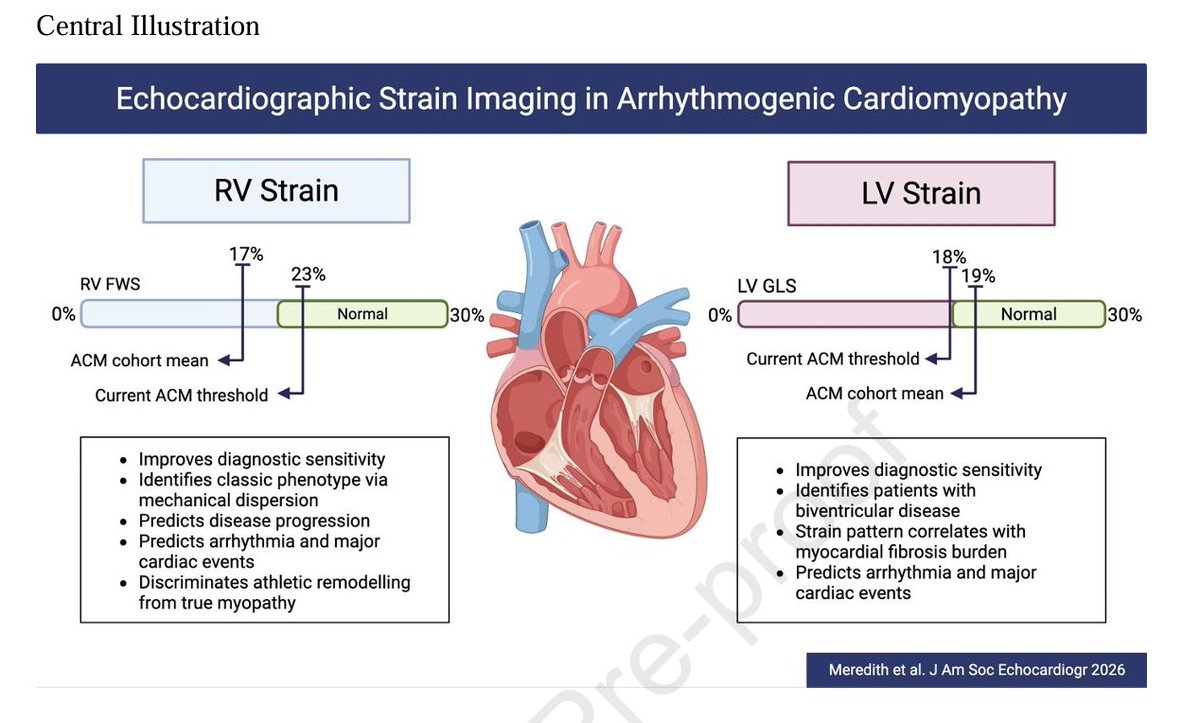

🔴State-of-the-Art in Echocardiographic Strain Imaging of Arrhythmogenic Cardiomyopathy @ASE360 #Cardiology #CardioEd #echofirst #Strain

🔴State-of-the-Art in Echocardiographic Strain Imaging of Arrhythmogenic Cardiomyopathy @ASE360 #Cardiology #CardioEd #echofirst #Strain